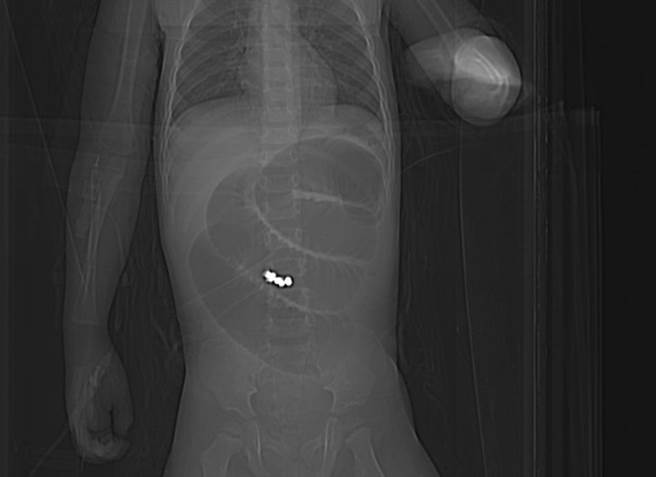

童综合医院一般外科医师张孟浩笔指处即为巴克球在小肠位置。(陈淑娥摄)

王姓幼儿因持续3天出现呕吐症状,且逐渐不太愿意吃东西,家人紧急带至童综合医院急诊室就医,医师诊疗并进行X光检查后,发现小肠处有异物;紧急会诊小儿外科主任郭敏勇与一般外科医师张孟浩,再进行断层扫瞄检查后,研判男婴小肠内不只1颗圆形异物,且已造成肠阻塞。

郭敏勇进行阻塞部位的小肠切除手术,并将异物取出,发现该幼儿吞进了8颗巴克球导致,因巴克球的超强磁性造成小肠的空肠与迴肠吸附在一起,且在肠道间形成廔管,还好没有造成肠液外漏或腹膜炎等严重情况,手术顺利恢復良好,住院一周即返家休养。